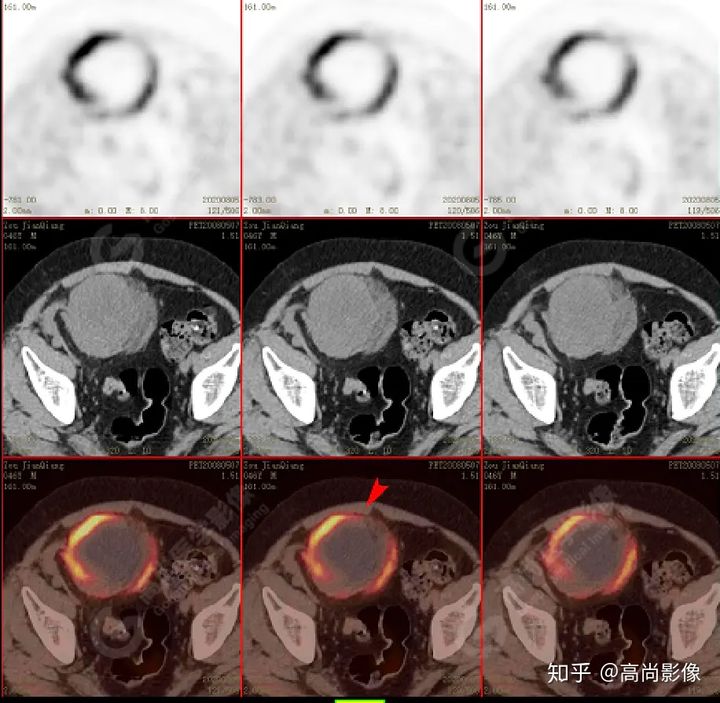

PET/CT檢查

↑移植腎下部等密度腫塊,代謝環(huán)狀增高,SUVmax13.4,中心代謝缺損